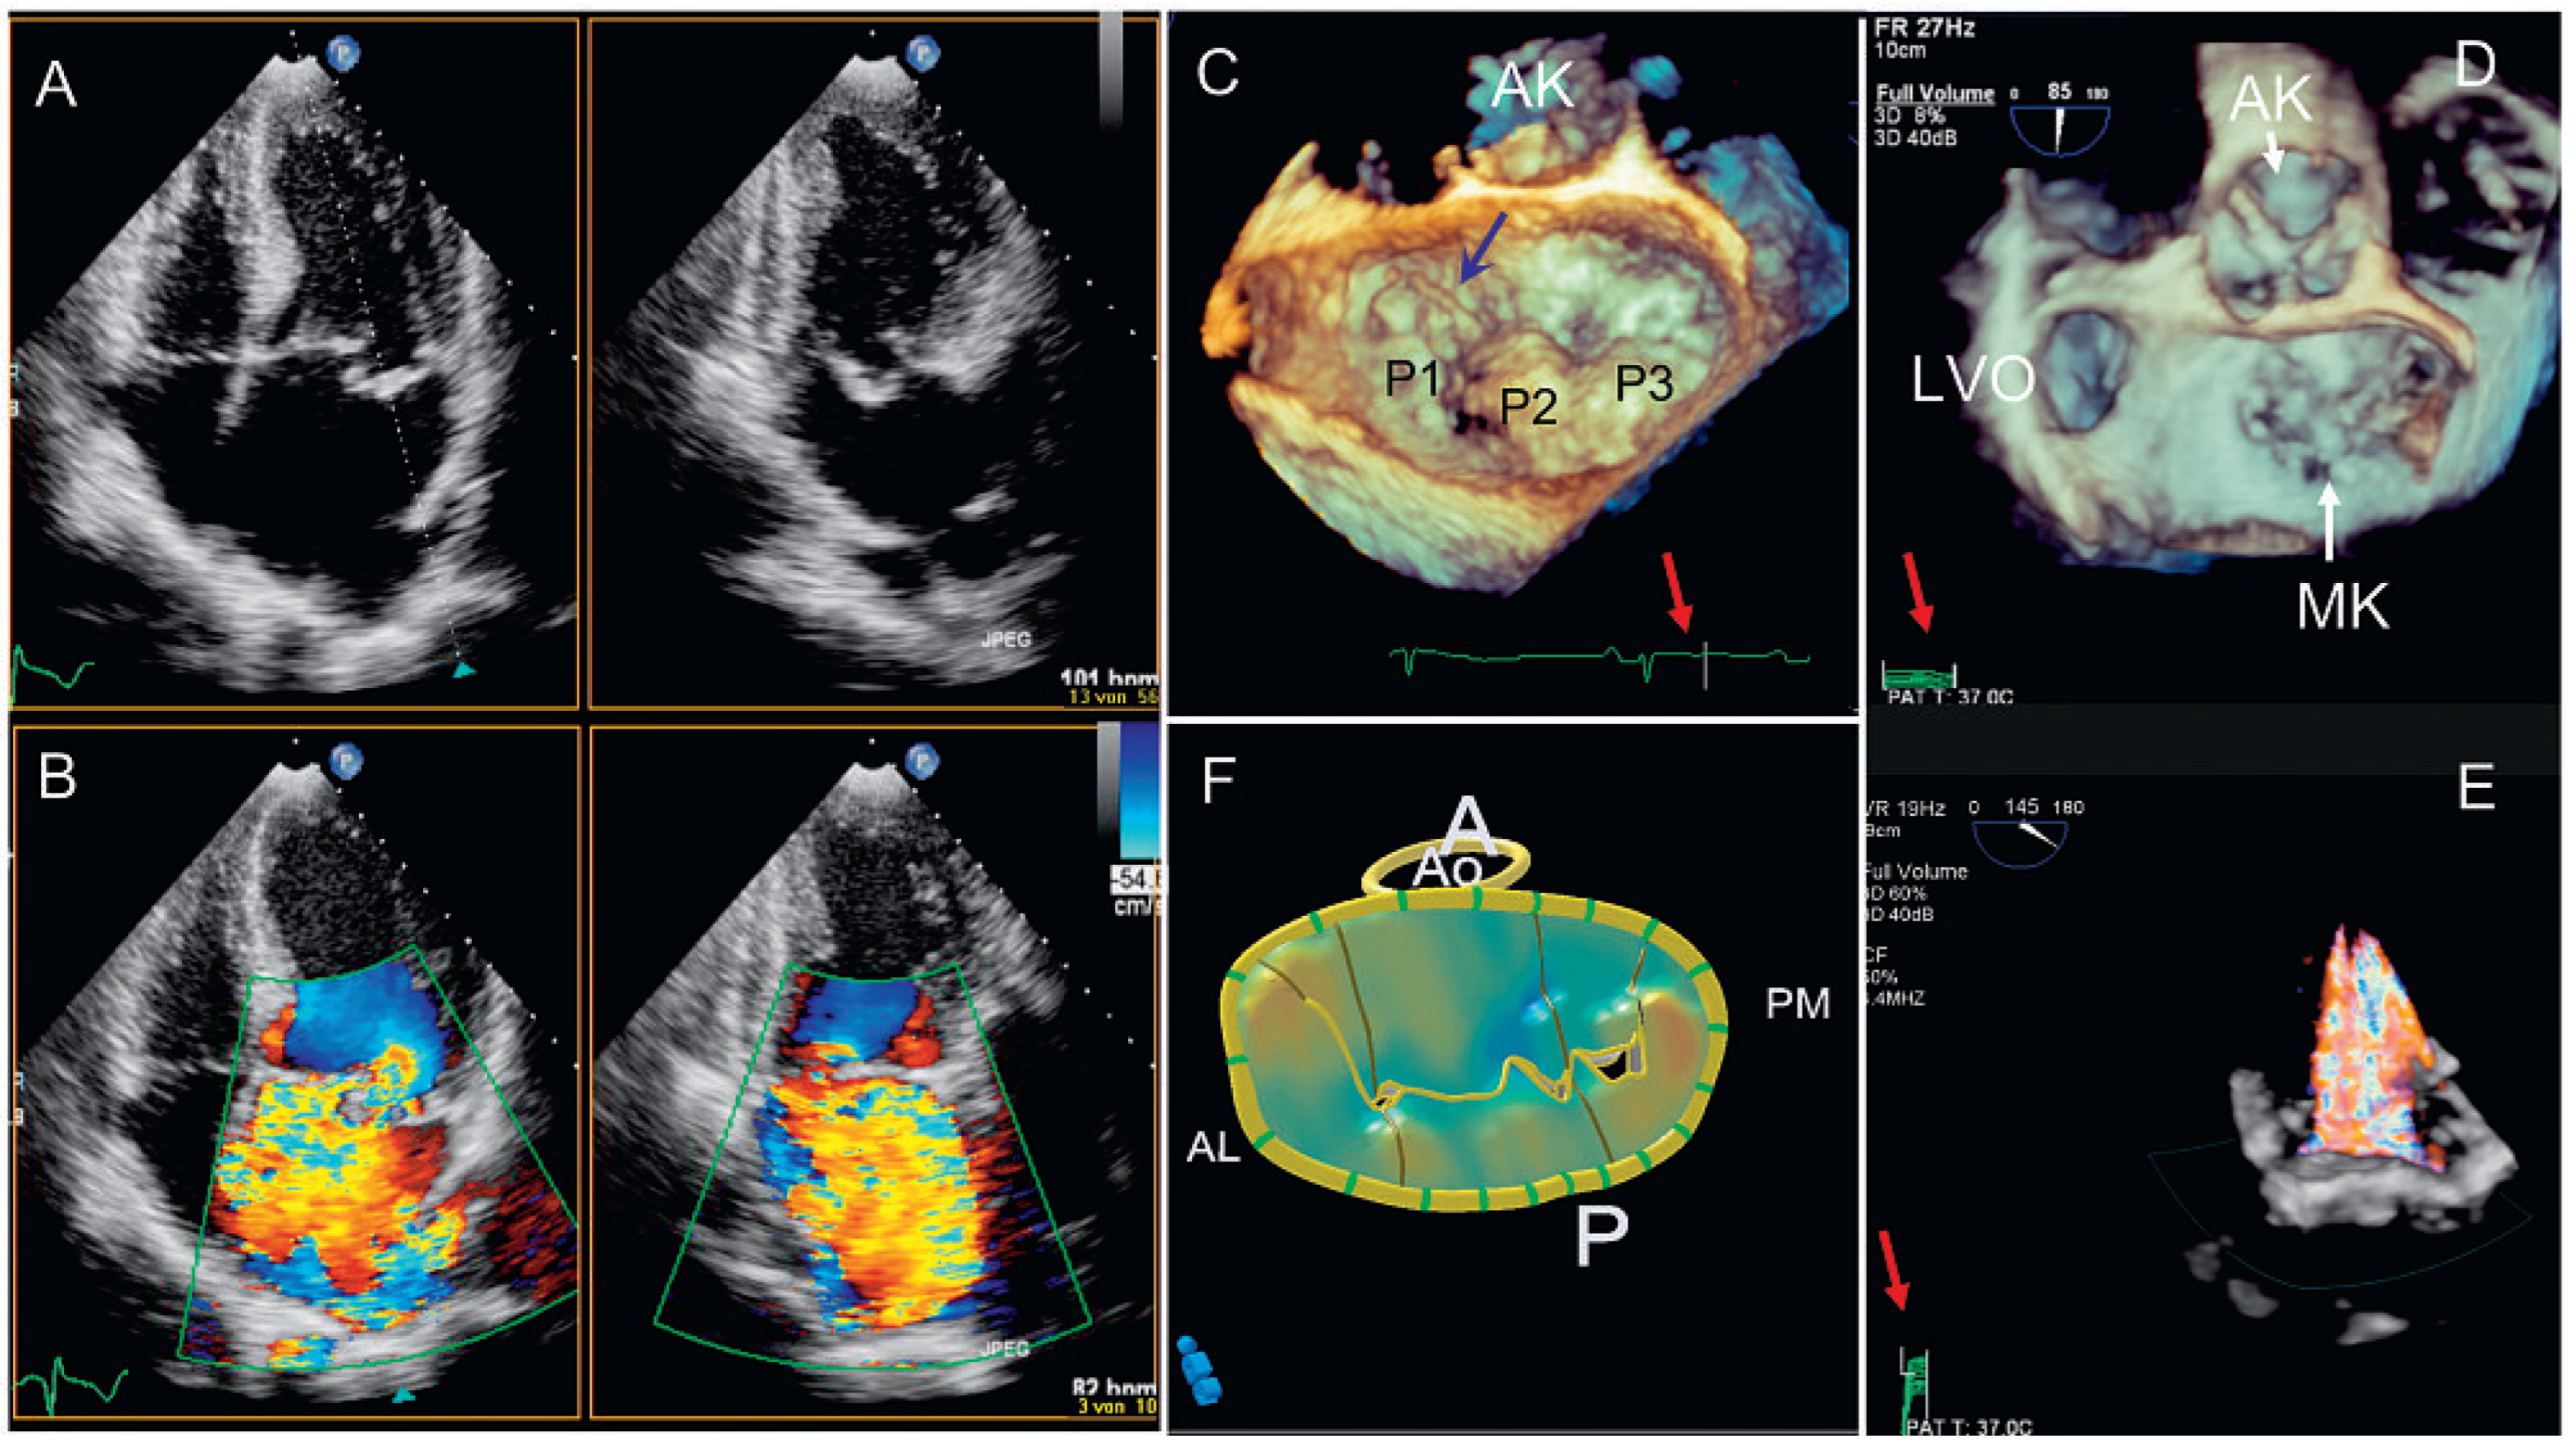

- «xPlane»: die Möglichkeit, gleichzeitig mehrere verschiedene Ebenen zu untersuchen, die in einem vom Untersucher wählbaren Winkel zu einander stehen (Abb. 1A). Zuschalten des Farb-Dopplers möglich (Abb. 1B).

- «3D zoom»: Echtzeit(«live»)-Untersuchung eines pyramidenartigen (dreidimensionalen) Sektors von bis zu 90° × 90° (Abb. 1C). Farb-Doppler nur in der neusten Generation der Geräte möglich.

- «full volume»: Aufnahme eines pyramidenförmigen (dreidimensionalen) Sektors, zusammengesetzt aus 4–7 Untersektoren (keine Echtzeit, Abb. 1D). In der neusten Generation der Geräte Aufnahme in einem Herzschlag. Farb-Doppler möglich (Abb. 1E).